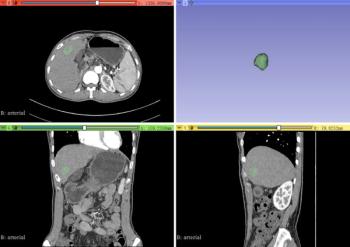

A new study showed that the computed tomography radiomics nomogram model had 21.7 percent higher accuracy, 16.7 percent higher sensitivity and 23.5 higher specificity in comparison to a clinical model in a validation cohort.